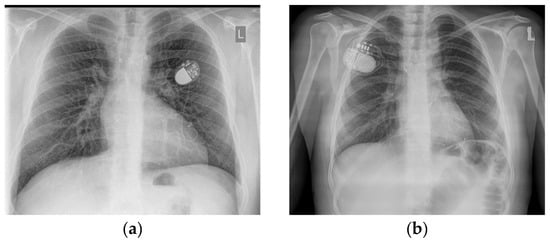

| Device implanted (VVI/DDD) | 6 (12%) |

| VVI—5, DDD—1, 2 devices removed because of cardiac device-related infective endocarditis |